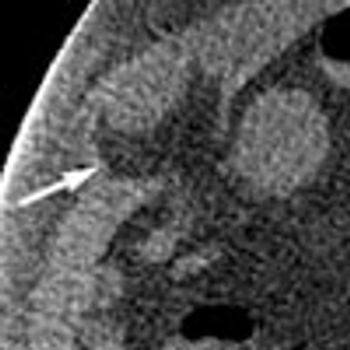

A 48-year-old woman with hypertension, HIV infection, anemia, and chronic kidney disease presented with generalized body weakness and diarrhea of several months’ duration.